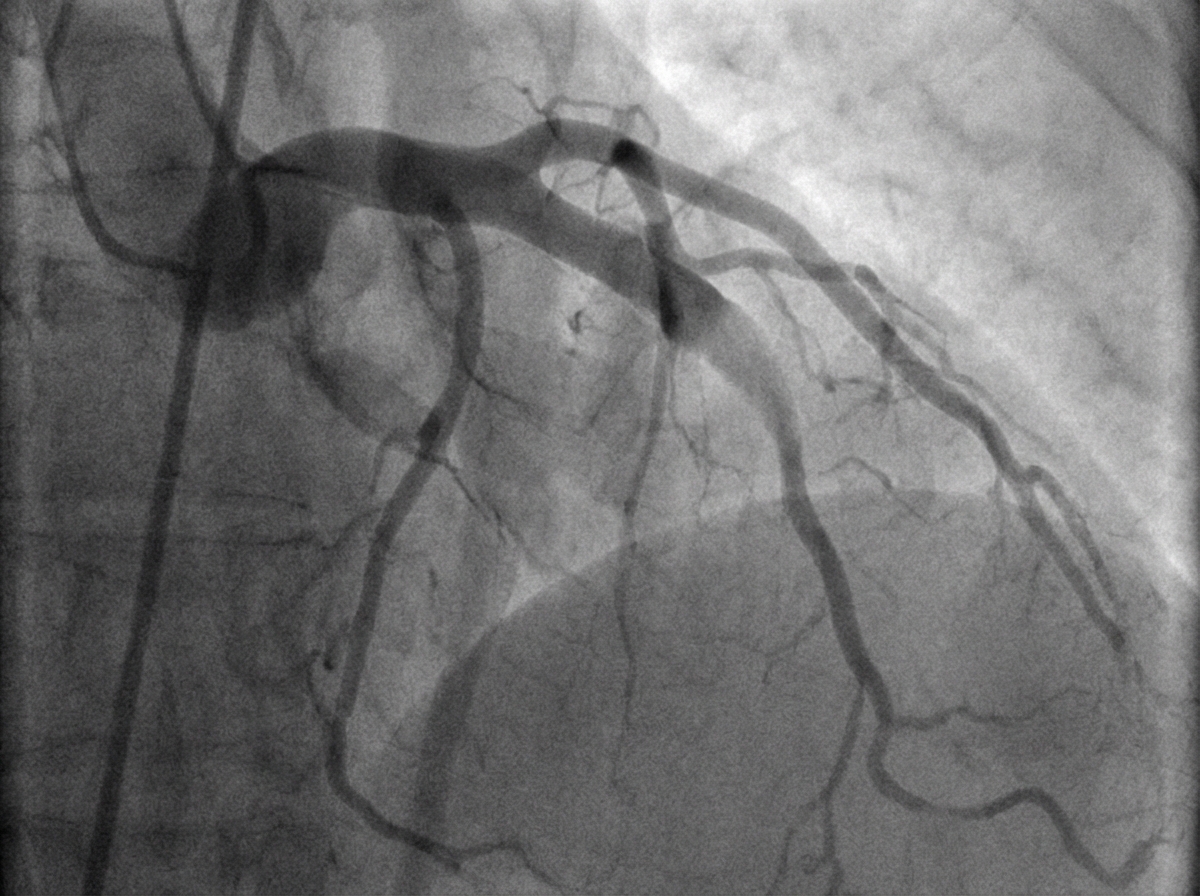

A 54-year-old woman is brought to the emergency department because of a 2-hour history of nausea and retrosternal chest pain. She has a 15-year history of type 2 diabetes mellitus. Her current medications include atorvastatin, metformin, and lisinopril. She is diaphoretic. Her serum troponin level is 3.0 ng/mL (N: < 0.04). She undergoes cardiac catheterization. A photograph of coronary angiography performed prior to percutaneous coronary intervention is shown. An acute infarct associated with the finding on angiography is most likely to manifest with ST elevations in which of the following leads on ECG?

Explanation: ***V1–V6*** - The angiography shows a significant occlusion in the **left anterior descending (LAD) artery** - LAD occlusion causes **anterior wall myocardial infarction** - Anterior MI manifests with **ST elevations in precordial leads V1–V6** - This is the classic ECG pattern for LAD territory infarction *V3R–V6R* - These right-sided precordial leads indicate **right ventricular infarction** - RV infarction is associated with **proximal right coronary artery (RCA) occlusion** - Not consistent with the LAD occlusion shown in the angiography *I, aVR* - Lead **aVR ST elevation** (especially >1 mm or greater than V1) suggests **left main coronary artery occlusion** or severe multi-vessel disease - This pattern typically shows widespread ST depression in other leads - Does not specifically indicate isolated LAD occlusion *II, III, and aVF* - ST elevations in these inferior leads indicate **inferior wall myocardial infarction** - Inferior MI is caused by **right coronary artery (RCA)** occlusion (80%) or left circumflex artery (20%) - Not associated with LAD occlusion *V7–V9* - These posterior leads indicate **posterior wall myocardial infarction** - Posterior MI results from **left circumflex artery** or dominant RCA occlusion - Not the primary finding with LAD occlusion